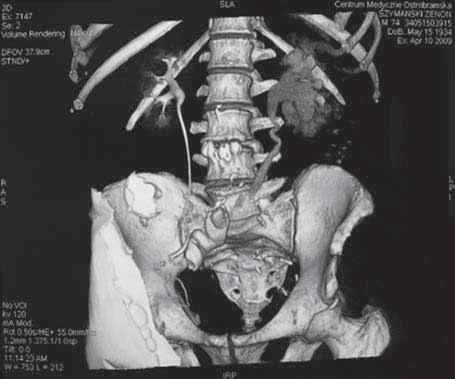

Rycina 87.4. ileal conduit a, ).